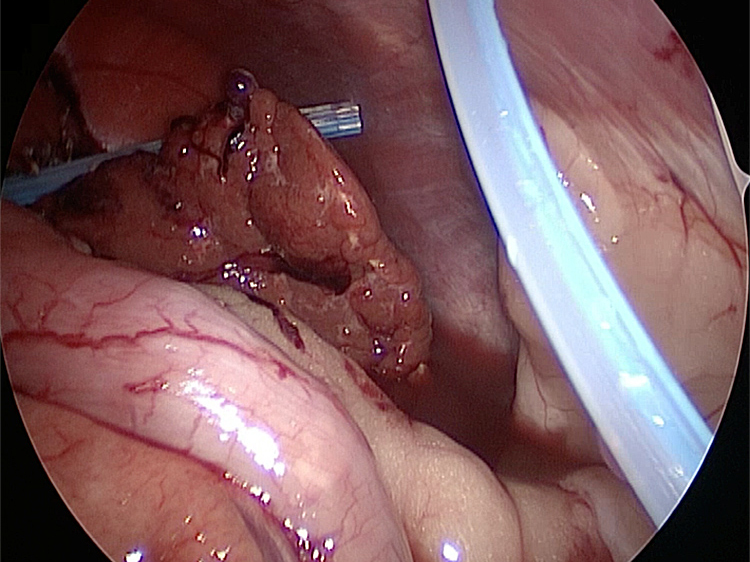

胆嚢の周囲の脂肪や膵臓、十二指腸が激しく癒着し剥離が困難な状態でした。胆嚢は全く確認することができませんでした。

少しずつ癒着を剥がして胆嚢が確認できるようになってきました。 こんなに癒着していることはあまりないので過去に膵炎や胆嚢炎を起こし苦しい時期があったことが推測されました。 それにしてもなかなか胆嚢はでてきませんでした。

胆嚢(矢印)の取り囲むように肝臓や腸が癒着していました。肝臓の表面はボコボコしています。